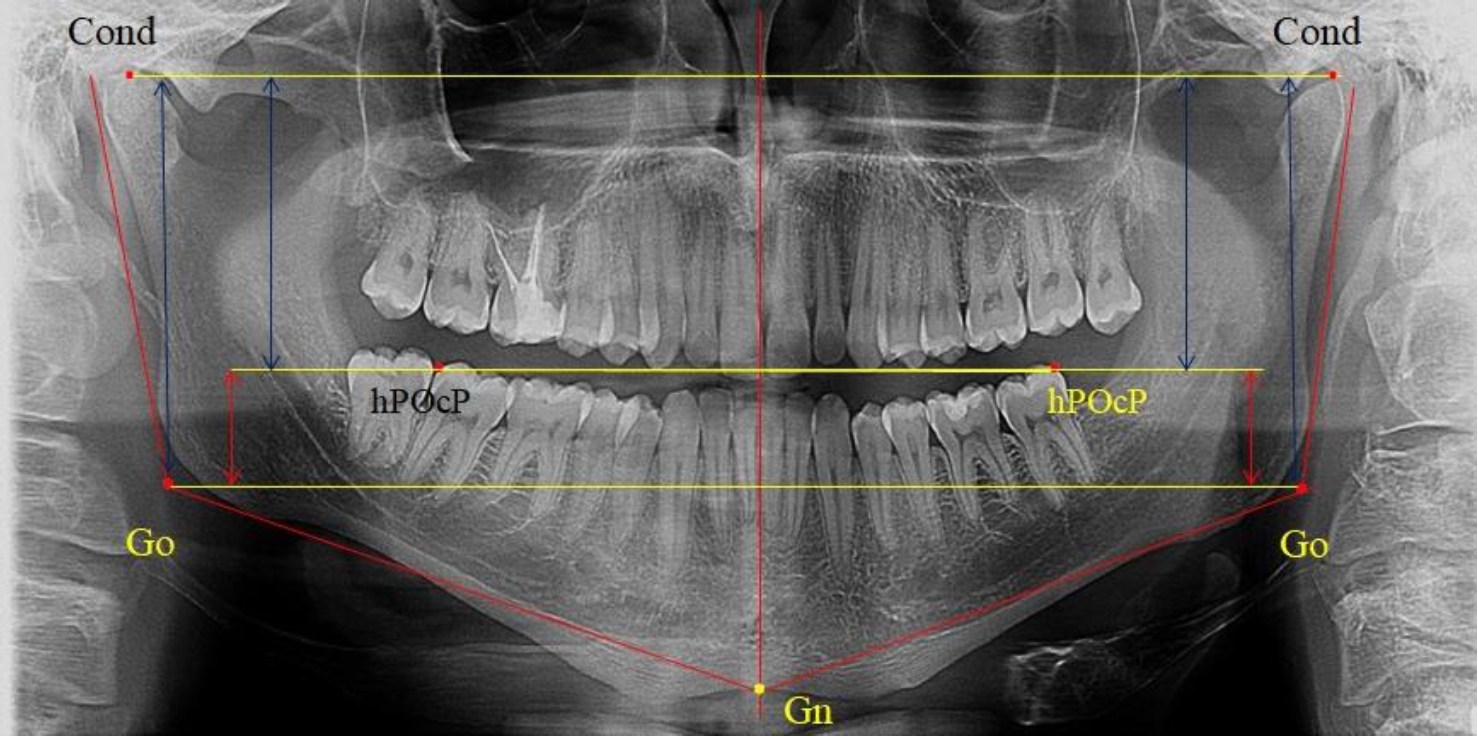

Во 2-ю подгруппу был включен 21 комплект телерентгенограмм и ортопантомограмм [или (28,38 ± 5,24) %], на которых средняя величина отношения верхней части ветви к нижней составляла 1,63 ± 0,03, что было достоверно меньше показателя, полученного по группе в среднем и в 1-й подгруппе.

Визуально параметры ветви отличались от первой группы (рис. 3).

Рис. 3. ОПТГ пациента 2-й группы с уменьшенным коэффициентом соотношения частей ветви нижней челюсти

Высота ветви составляла (62,75 ± 1,42) мм и достоверных различий по этому показателю не отмечено. Максимальная высота была 73 мм, а минимальная – 55 мм. Высота верхней части составляла (38,81 ± 0,76) мм, что было достоверно меньше, чем у людей 1-й подгруппы.

В то же время высота нижнего отдела ветви была (23,94 ± 0,73) мм, и показатель отличался в большую сторону по сравнению с аналогичным размеров в 1-й подгруппе.